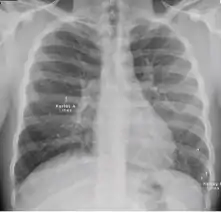

7. Other - Any other finding suggestive of active TB, such as miliary TB. Miliary findings are nodules of millet size (1 to 2 millimeters) distributed throughout the parenchyma.